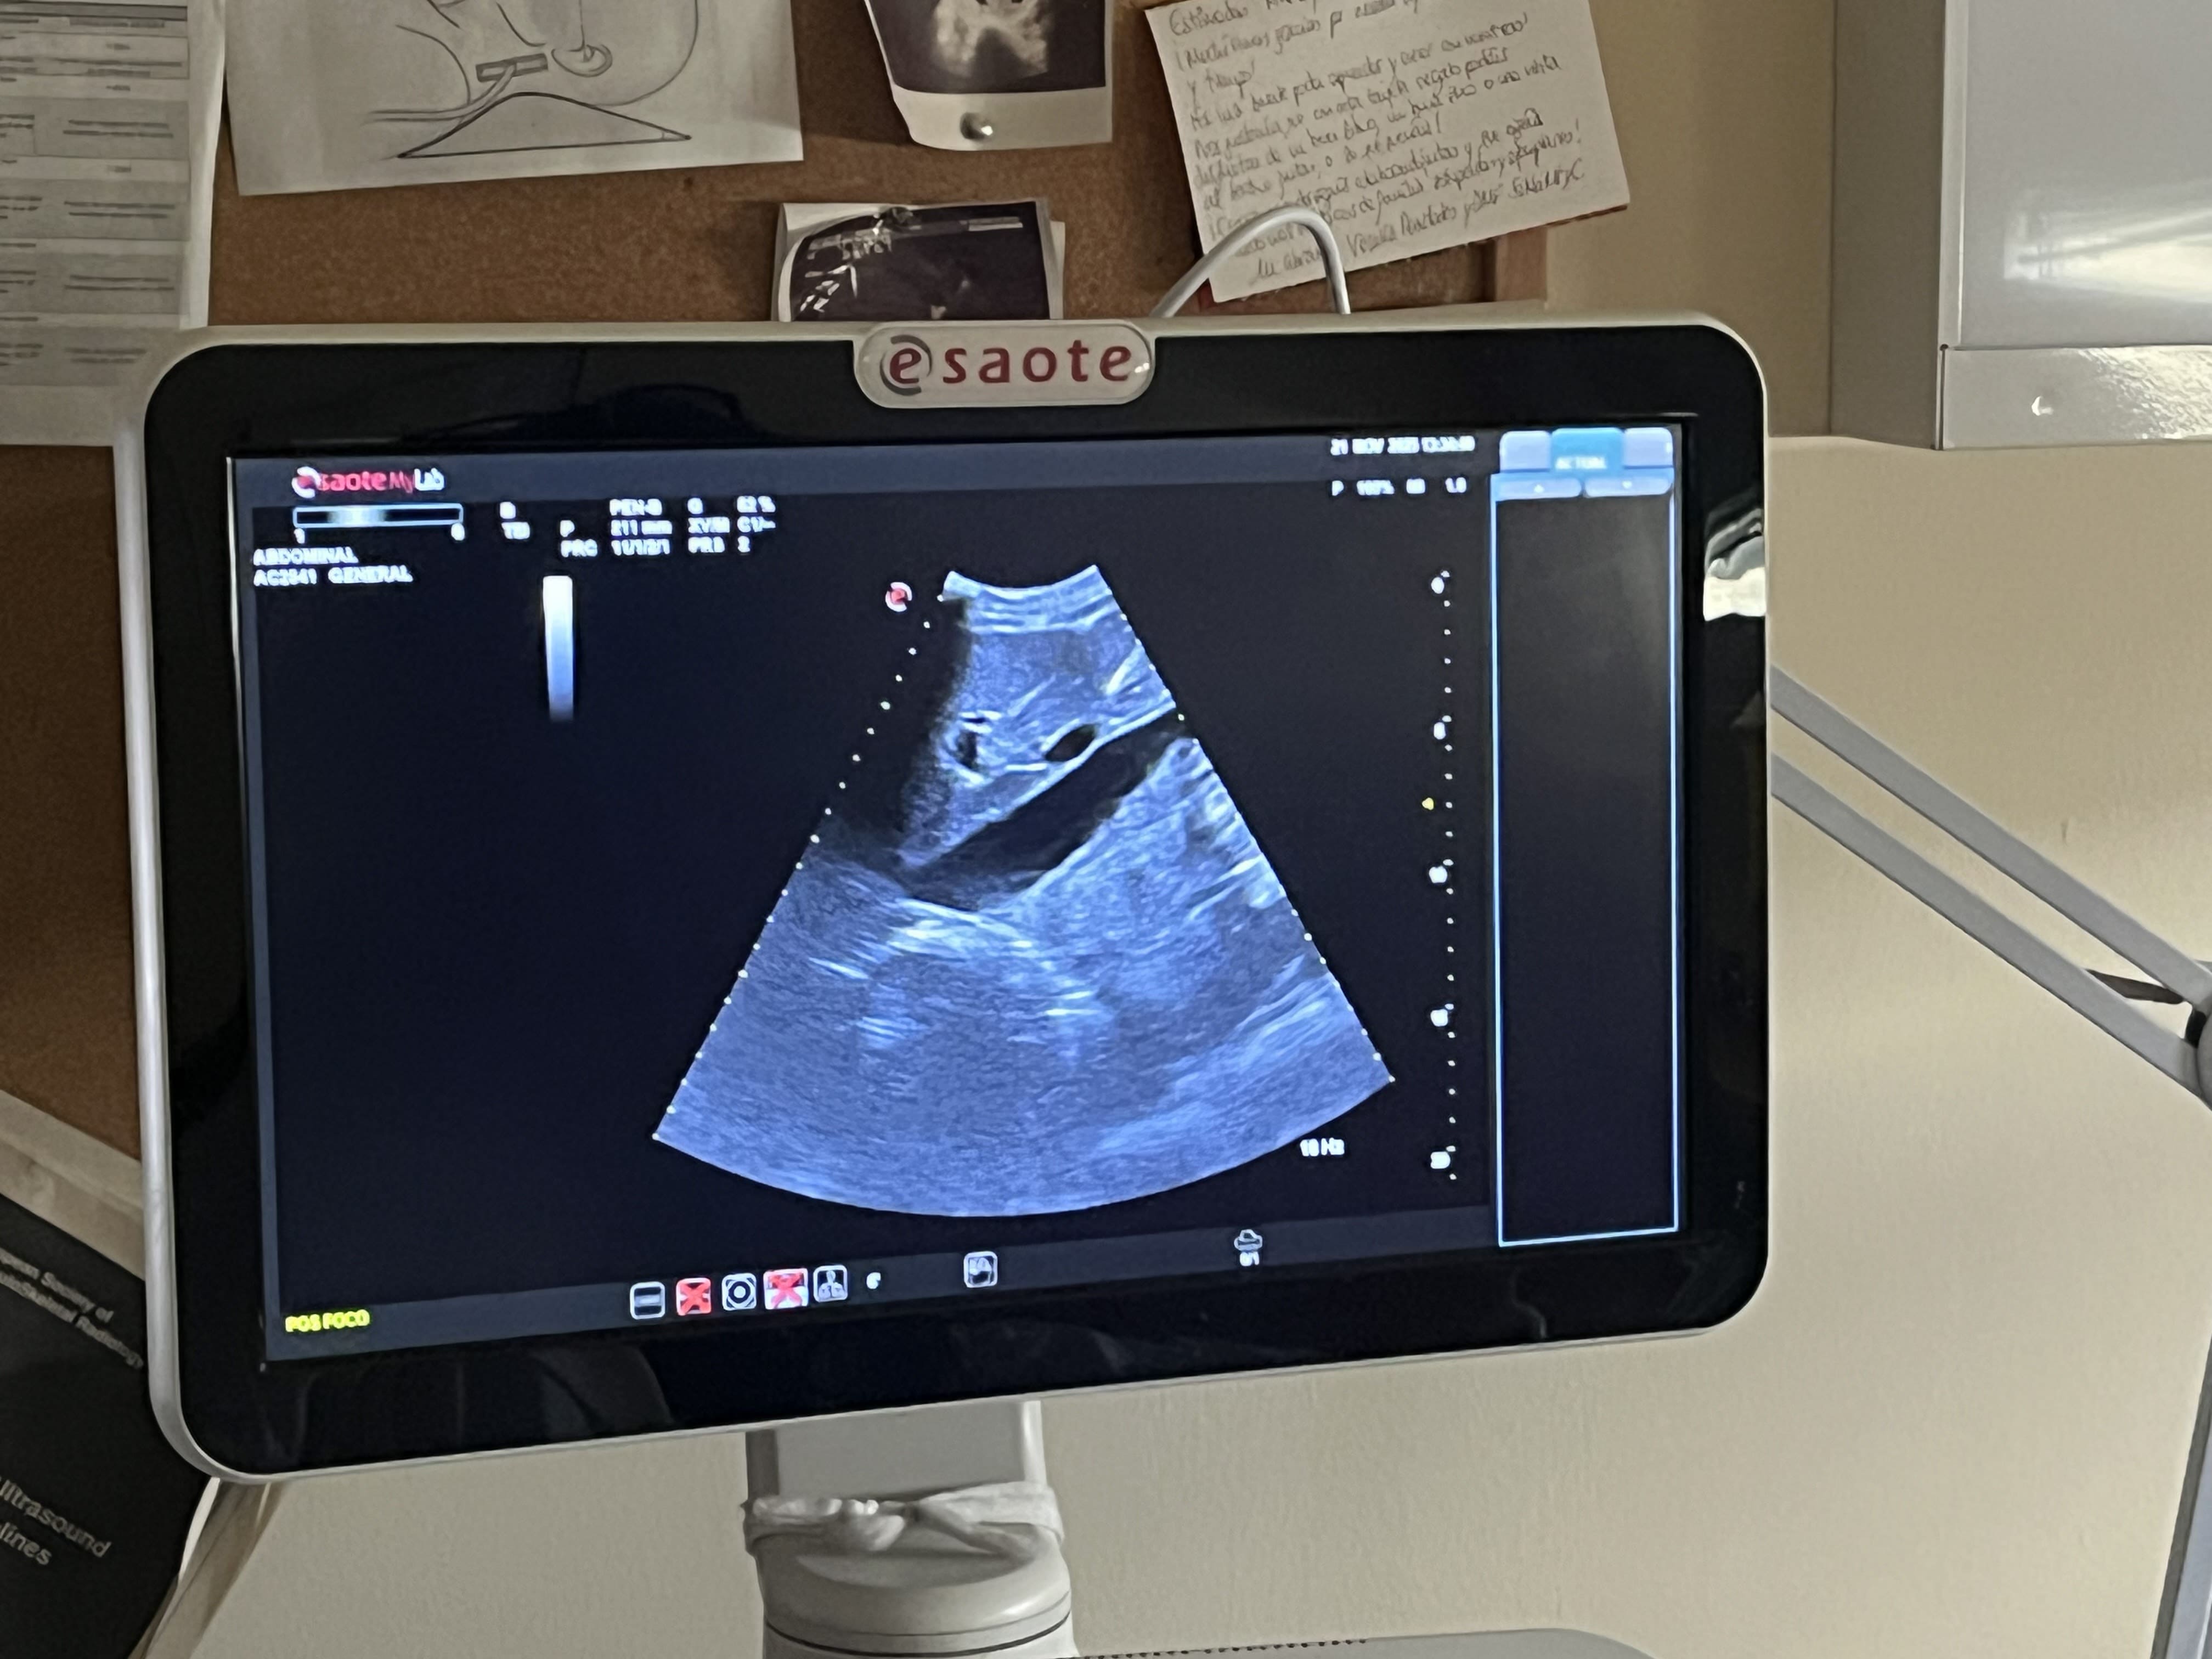

Utilizar la ecografía nos permitió mostrar al paciente lo que estábamos valorando, explicar hallazgos en tiempo real (litiasis, líquido articular, quistes benignos, etc.) y hacerles partícipes del proceso diagnóstico. Esta experiencia cambió el tono de muchas consultas: pacientes inicialmente evasivos se mostraban más interesados, participativos y confiados. La ecografía se convirtió en un lenguaje compartido, visual y transparente, que ayudó a superar barreras y a fortalecer el vínculo entre residente y paciente.

La ecografía clínica, utilizada como apoyo explicativo además de diagnóstico, facilita el acercamiento entre residentes y pacientes, mejora la comprensión del proceso, refuerza la confianza mutua y favorece una relación más cercana y participativa. Es una herramienta que transforma una potencial distancia en una oportunidad de conexión, aprendizaje y colaboración.